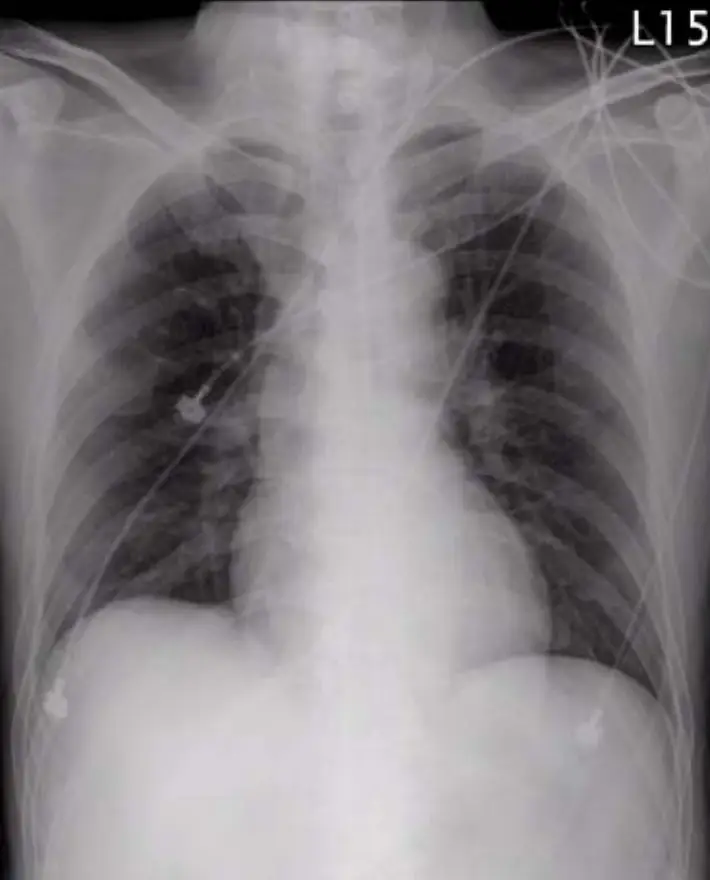

圖一:胸部X光(Chest X-ray,AP view)

本片為急診床邊AP位胸部X光,可見多條心電圖監測電極線跡。心臟輪廓略偏大,但未達明顯心臟肥大標準(CT ratio 接近正常)。肺野呈現輕度間質性浸潤,提示可能有輕微肺水腫初兆,與左心室功能障礙一致。縱膈寬度無明顯增寬,可基本排除主動脈剝離(aortic dissection)。無明顯氣胸、大量肋膜積液或肺葉塌陷。右中肺野可見一小圓形緻密影,疑為心電圖電極扣。